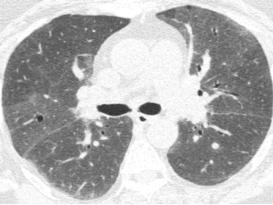

图:(从左至右)治疗前、脱离暴露+激素治疗10月、停激素18月

病例:男性,33岁,劳力性呼吸困难4年,加重3月,在治疗之前,我们看到的影像有些磨玻璃影、马赛克征,还有小叶中央型结节,并进行了外科肺活检。患者在从事铸造工作过程中间断接触异氰酸酯。停止工作暴露,并糖皮质激素经过治疗后,病情好转,但停用激素后又出现了肺部弥漫的磨玻璃影,肺功能也有所下降。